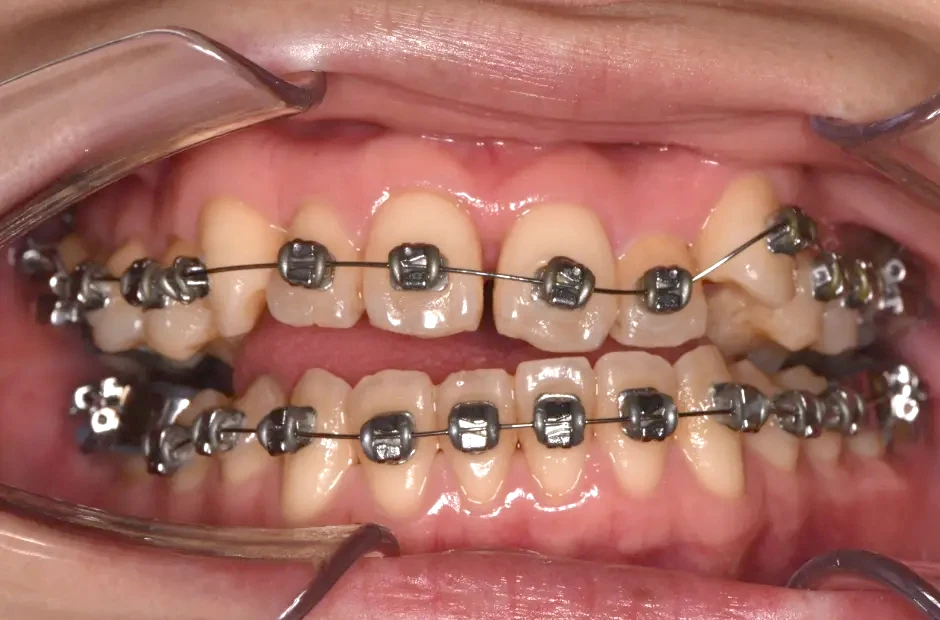

叢生

| 診断名・主訴 | 叢生 |

|---|---|

| 年齢・性別 | 43歳・女性 |

| 治療期間・回数 | 2年7か月 27回 |

| 治療に用いた主な装置 | 舌側矯正 |

| 抜歯部位 | 両顎4,4 |

| 治療費 | 100万円(税抜) |

| リスク・副作用 | 装置による違和感・疼痛・歯肉退縮・歯根吸収・虫歯のリスクなど |

治療中